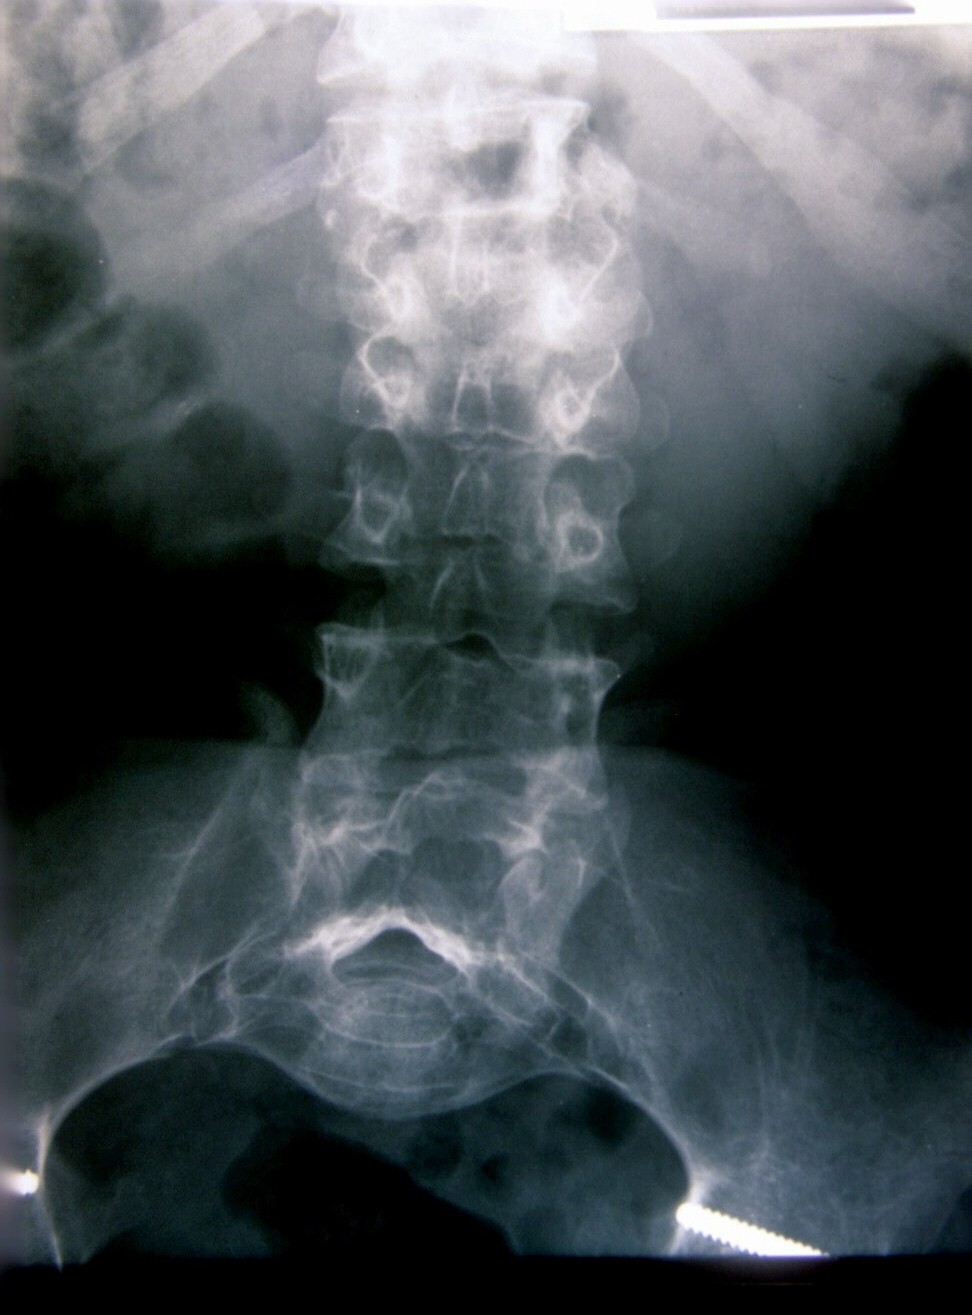

Seudoacondroplasia. [Pseudoachondroplasia]

2. Beals RB, Horton W. Skeletal dysplasias: an approach to diagnosis. J Am Acad Orthop Surg 1995;3:174-1.

3. Herring JA. Tchadjian´s. Pediatric Orthopedic, 3rd ed. Philadelphia: Saunder; 2002:1523-5.